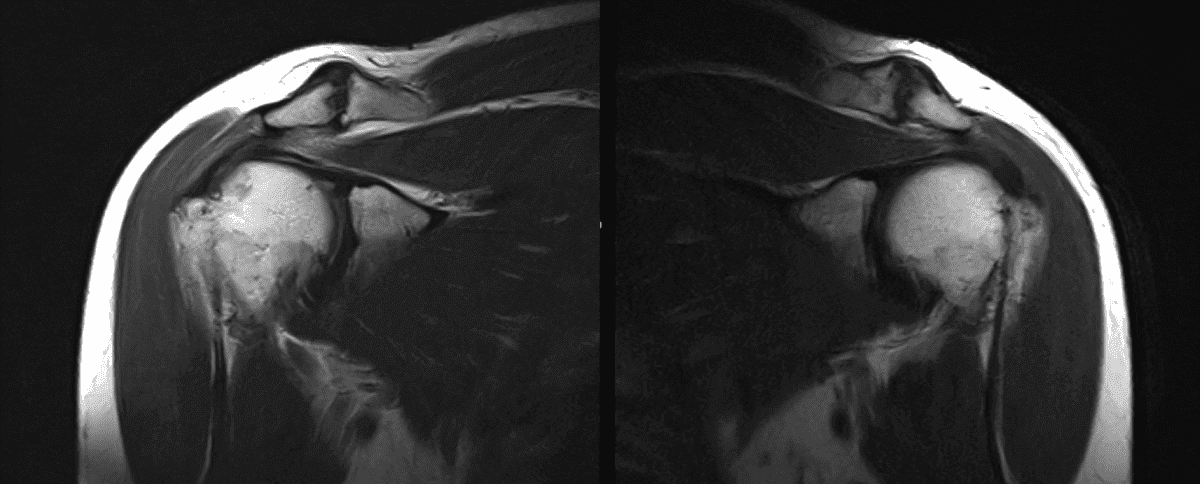

El paciente presentó resultados de resonancia magnética para ambos hombros. Para el desgarro intersticial derecho de bajo grado del tendón supraespinoso posterior. Tendinosis supraespinosa leve y subescapular.

Para el izquierdo, una ruptura intersticial de bajo grado del tendón supraespinoso posterior sobre una tendinosis de fondo leve. Desgarro del labrum posterior-superior. Artrosis articular acromioclavicular leve.

Resonancia magnética sin contraste en el hombro izquierdo